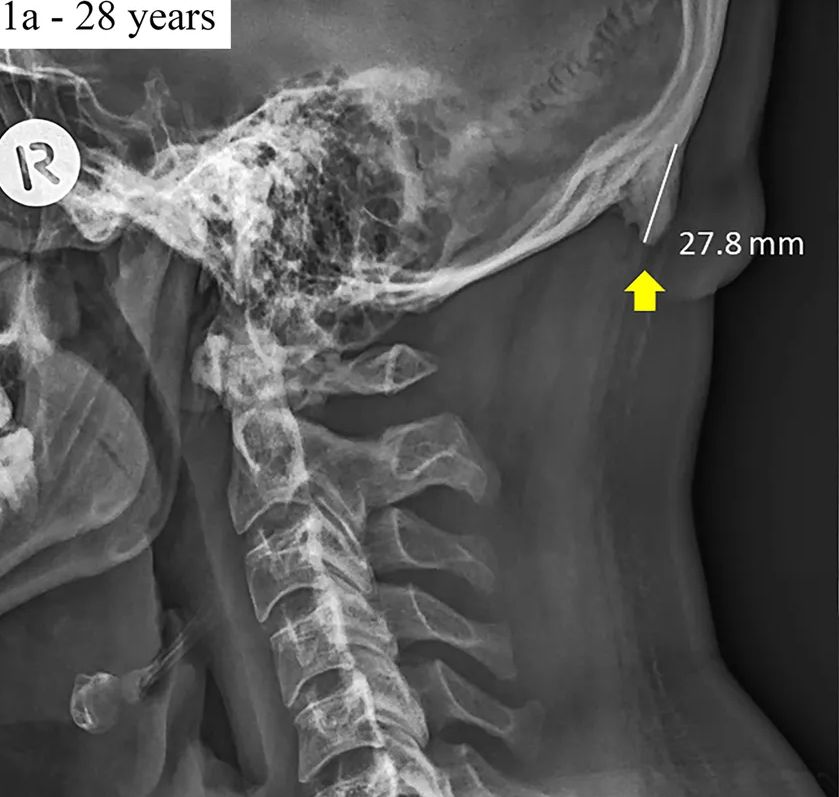

| Az ausztráliai Sunshine Coast Egyetem tudósai ezerkétszáz 18-86 év közötti ember koponyáját vizsgálták röntgenfelvételen. Nem csupán csontos deformitásokat kerestek, a vizsgált személyek testtartását is elemezték annak érdekében, hogy összefüggést találjanak a két jelenség (csontkinövés és helytelen testtartás) közt. A páciensek 33 (!!!) százalékánál bukkantak kóros csontkinövésre a nyakszirtcsont legkiállóbb részén (lásd a fenti képen). Még inkább megdöbbentő, hogy a 18-30 év közötti fiataloknál jóval gyakrabban fordul elő a deformitás, mint a 30 éven felülieknél; több mint 40 százalékuknál fedezték fel a karomszerű nyúlványt. A legnagyobb „fejentyű” (a szót a sarkantyú kifejezés után szabadon költöttem, az indokot lásd később) 3 cm (!!!) hosszú, azaz nagyjából akkora, mint egy nagytestű kutyus szemfoga. A deformitást a testtartásvizsgálatok eredményeivel összevetve a kutatók arra a következtetésre jutottak, hogy a csontkinövés kialakulásában elsődleges szerepet játszik a helytelen terhelések következtében kialakuló ún. előrehelyezett fejtartás. |

Az inion (protuberantia occipitalis externa) a nyakszirtcsont legkiállóbb része, ahonnan a tarkószalag és a trapézizom egyes rostjai erednek.

Már több mint egy évszázaddal ezelőtt észrevették, hogy idős korra a sok-sok évnyi káros terhelés következtében kialakuló ún. előrehelyezett fejtartás (EFT) miatt ritkán ugyan, de kisebb-nagyobb csontkinövés jelenhet meg ezen a területen. Az EFT következtében ugyanis az inionról eredő tarkószalag és a trapézizom felső része egyaránt krónikusan túlterheltté és feszessé válik, hisz ezekre a lágyrészekre hárul az előrehelyeződés miatt megtöbbszöröződő súlyú fej megtartása (hogy pontosan milyen mechanizmus játszódik le ilyenkor, azt részletesen kifejtettem ebben az írásomban).

A feszessé váló lágyrészek gyakorlatilag folyamatosan tépik és irritálják eredési pontjukon a csonthártyát, így a szervezet védekező mechanizmusként megerősíti az adott területet, mégpedig úgy, hogy további csontot „épít” a meglévőre.